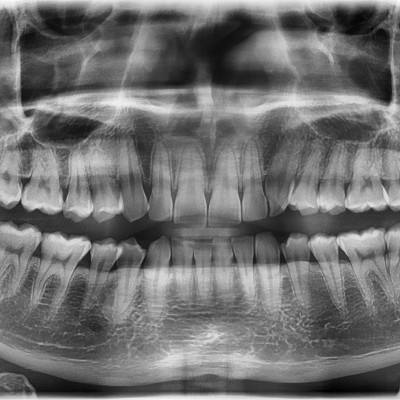

#18,28,38,48 사랑니 발치 N새글 #18,28,38,48 사랑니 발치 구강 외과 전문의가 당일 발치했습니다. --------------------..